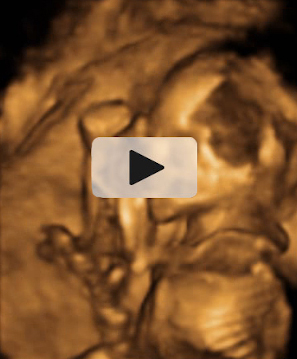

Ecografía Embarazo 2D y 3D Semana 20 - MALFORMACIONES FETALES

Ecografía Embarazo 4D Semana 20 - MALFORMACIONES FETALES